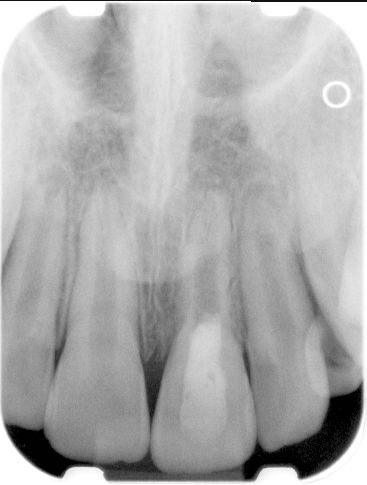

Clinical procedure: Regeneration of the endodontic pulp space is indicated for cases with very thin dentinal walls and an open apex that is more than 1 mm in diameter radiographically (Figure 4). Disinfection of the root canal system is performed using sodium hypochlorite irrigation followed by a triple antibiotic paste dressing that is left in place for 1 week. At the second visit, ethylenediaminetetraacetic acid (EDTA) is used to condition the dentin walls, which results in the release of growth factors, and bleeding is stimulated in the periapical tissues (where stem cells are located), with the aim of filling the pulp space with a stable blood clot, which would serve as the scaffold. MTA is then placed at the canal orifice in contact with the clot to protect it from coronal microleakage (Figure 5 and Figure 6). In time, the clot should be replaced with a reparative tissue of variable composition, and the root walls should continue to thicken due to the deposition of a dentin-like material on the pre-existing root dentin27,28 (Figure 7 and Figure 8).

Fig 4. Preoperative radiograph showing aggressive external root resorption and thin dentinal walls.

Figure 4

Fig 5. Working length confirmation.

Figure 5

Fig 6. Postoperative radiograph.

Figure 6

Fig 7. 1-year follow-up showing a healthy lamina dura and root development.

Figure 7